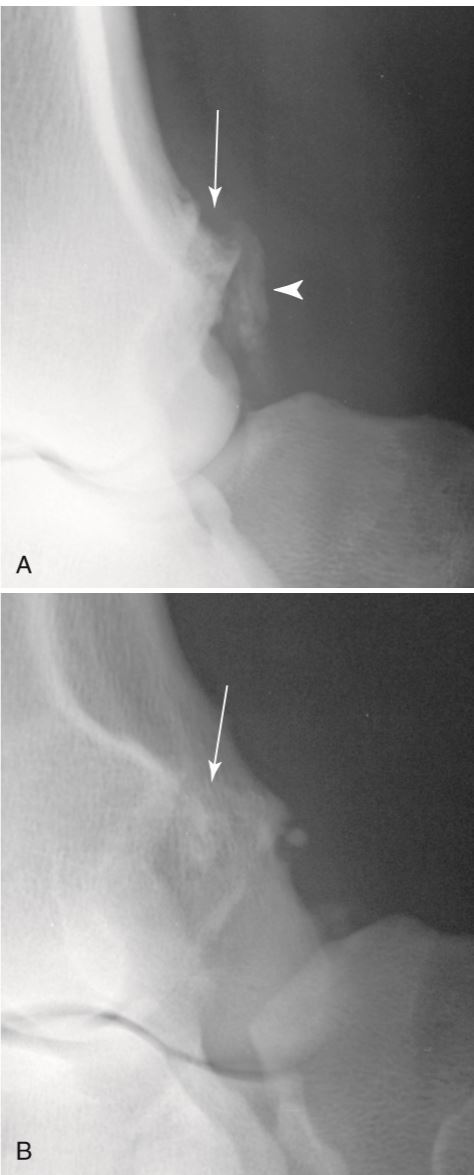

What are the arrows pointing to?

Intracapsular fat. Showing that there is no joint effusion. B has joint effusion.